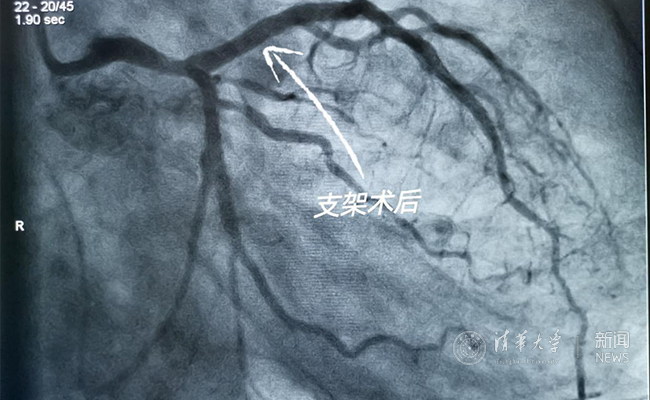

2019.05国产冠脉生物可吸收支架在清华大学第一附属医院正式启用

作为北京地区首家正式引入国产冠脉生物可吸收支架单位,5月20日,清华大学第一附属医院(北京华信医院)心脏中心主任苗立夫团队顺利完成该院首例生物可吸收支架植入。